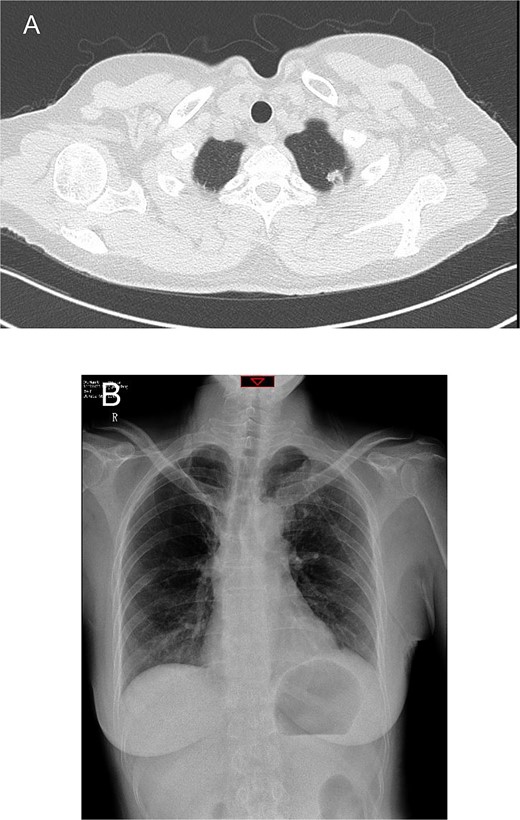

A 54-year-old female presented with a solid nodule measuring 11 mm × 8 mm in the S1+2 segment of the left upper lobe, detected on preoperative computed tomography (CT) (Fig. 1A). She had a history of right upper lobe segmentectomy performed 2 years prior, with pathology revealing atypical hyperplasia. We planned to proceed with a uniportal VATS left upper lobe wedge resection.

Preoperative chest computed tomography and postoperative day one chest X-ray. (A) Computed tomography shows a solid nodule in the S1+2 segment of the left upper lobe measuring 11 mm × 8 mm. (B) Postoperative day one chest X-ray indicates routine postoperative changes.

On the first postoperative day, the patient’s vital signs were stable, with ~200 ml of serosanguineous fluid drained from the chest tube. Chest X-rays showed normal findings on the day after the operation (Fig. 1B). The patient was mobilized on the second day, with chest tube drainage decreasing to 100 ml, allowing for chest tube removal.